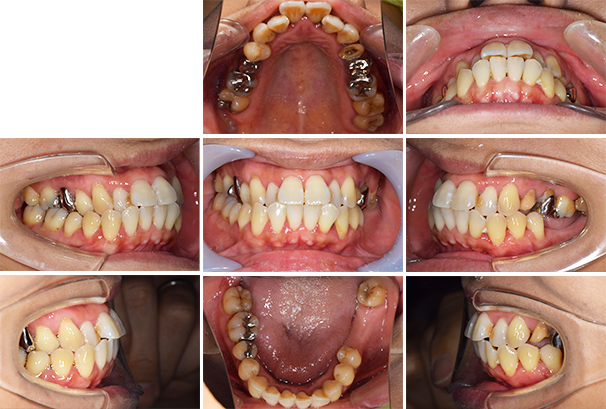

口腔内写真

【担当医師所見】

咬合平面の整頓の必要性 有

交叉咬合、オーバージェットの是正

前歯舌側の歯石

歯周病の治療の必要性

ブラッシング方法の教授